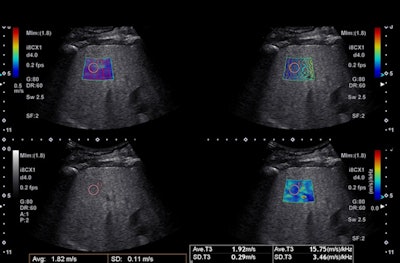

When shear waves are generated by the push-pulse of a focused ultrasound beam directly in the tissue, it's called acoustic radiation force impulse (ARFI). A convex or linear transducer transmits focused ultrasound pulses that are repeated several times in a short stint. B-mode tracking pulses detect the propagation velocity of the shear wave by measuring the difference in arrival time (time lag) between two points at known distances apart from each other, according to the article.

"ARFI-based techniques can be used for assessing the stiffness of other organs as well; however, the best application where shear-wave elastography can be considered a real breakthrough is for the noninvasive staging of liver fibrosis," Ferraioli said in an interview. "The deformation arising from tissue compression propagates laterally -- it's like when a stone is thrown in water and you see all waves. The speed of the propagation is directly related to tissue stiffness: The stiffer the tissue, the higher the speed. The speed can be converted in the measure of stiffness (kPa) using the Young's modulus and assuming that the tissue is purely elastic."

Shear-wave speed is nearly 1,000 times less than ultrasound velocity in soft tissue, with shear waves attenuating swiftly, whereas some do not propagate in simple fluids at all. Also, shear waves propagate faster in stiffer tissue than in softer tissue, a phenomenon that forms the basis for using SWE to differentiate between tissue types.